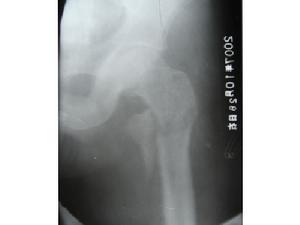

外傷後局部疼痛、腫脹、壓痛和功能障礙均較明顯,有時髖外側可見皮下瘀血斑,遠側骨折段處於極度外鏇位,嚴重者可達90°外鏇。病人多為老年人,傷後髖部疼痛,不能站立或行走。下肢短縮及外鏇畸形明顯,無移位的嵌插骨折或移位較少的穩定骨折,上述症狀比較輕微。檢查時可見患側粗隆升高,局部可見腫脹及瘀斑,局部壓痛明顯。扣擊足跟部常引起患處劇烈疼痛。往往需經X線檢查後,才能確定診斷,並根據X線片進行分型。

(3)、X線攝片可見骨折

股骨粗隆間骨折和股骨頸骨折的受傷姿勢,臨床表現大致相同,兩者容易混淆,應注意鑑別診斷,一般說來,粗隆間骨折因局部血運豐富、腫脹、瘀斑明顯,疼痛亦較劇烈,都比股骨頸骨折嚴重;前者的壓痛點多在大粗隆部,後者的壓痛點多在腹股向韌帶中點的外下方。X線片可幫助鑑別。

下肢短縮及外鏇畸形明顯,無移位的嵌插骨折或移位較少的穩定骨折,上述症狀比較輕微。檢查時可見患側粗隆升高,局部可見腫脹及瘀斑,局部壓痛明顯。扣擊足跟部常引起患處劇烈疼痛。往往需經X線檢查後,才能確定診斷,並根據X線片進行分型。

診斷明顯外傷史,患肢疼痛,活動受限。Х線片可確定骨折部位及移位情況。併發症肺炎;褥瘡;泌尿系感染患者多為高齡老人,首先注意全身情況,預防由於骨折後臥床不起而引起危及生命的各種併發症,如肺炎、褥瘡和泌尿系感染等。骨折治療目的是防止發生髖內翻畸形,具體治療方法應根據骨折類型、移位情況、患者年齡和全身情況,分別採取不同方法。